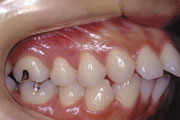

症例1:乱杭歯(叢生)